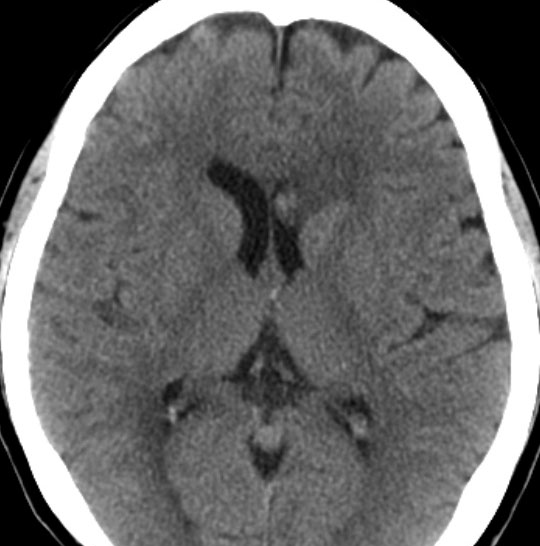

無症状で偶然発見された47歳女性の側脳室内上衣下腫

無症候で偶然発見された左側脳室前角尾状核頭に接したsubependymoma。定位脳生検で病理診断を得たましたが,3年間の観察で徐々に増大しました。左上が発見時,1年後(右上),2年後(左下),3年後(右下)

CTではやや低吸収,T1ガドリニウムでは低信号となりガドリニウム増強されません。小さな上衣下腫の場合は等吸収あるいは等信号のものも多いです。小さく点状に造影されている部分があるがこれは定位脳手術痕(track)です。

左中前頭回からの経皮室法 left middle frontal gyrus transcortical approach で全摘出できました(右図)。